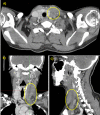

This clinical case presents an unusual case of Lemierre's syndrome (LS) in a young woman of 38-year-old. She arrived in the Emergency Department with a high fever and pharyngology resistant to antibiotic therapy with clarithromycin, ceftriaxone, and cortisone for two weeks. At the blood sampling, there is a marked leucocytosis, and the advice of the otolaryngologist is required given the strong pain in the throat. Due to the tonsillar abscess, a neck CT with a contrast medium is necessary for the otolaryngologist's opinion. The CT shows thrombosis of the jugular vein and left subclavian, with thickening of soft perivascular tissues; these findings suggest Lemierre's syndrome: a septic thrombophlebitis of the jugular vein that occurs as a complication of a peritonsillar abscess. The diagnostic process is then completed with a chest HR-CT, which reveals lung density and excavation areas suggesting tuberculosis. Blood culture reveals the presence of Veillonella Parvula (an anaerobic gram-negative coccus), sputum culture reveals the presence of some colonies of Enterobacter cloacae complex, real-time PCR examination on sputum reveals the presence of Streptococcus Pneumoniae and the borderline presence of rhinovirus. Microbiologists, after these results and neck and chest CT with a contrast agent, agree with the diagnosis of suspected LS at an early stage: a septic dissemination fortunately limited only to the neck and lungs region.